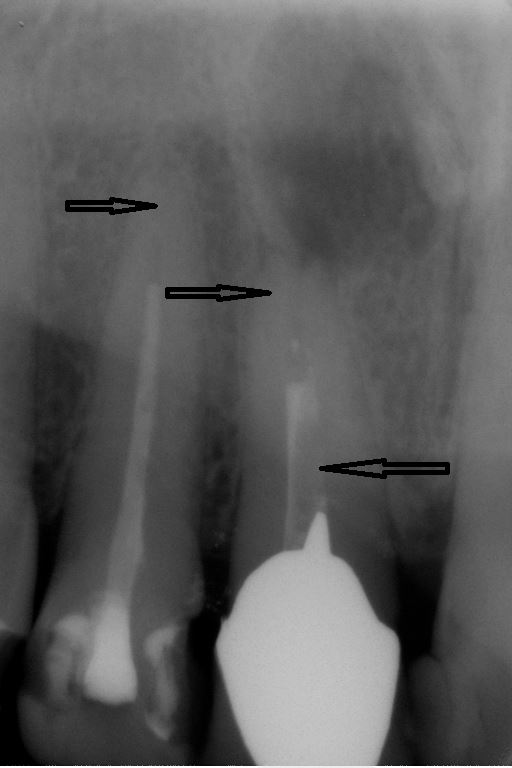

Fallbeispiel für einen komplexen Kanalverlauf

Mit Hilfe der elektronischen Längenmessung und digitalen Röntgenbildern können die Länge und Krümmung der Kanäle bestimmt und der Verlauf beurteilt werden.

Unter örtlicher Betäubung ist die Behandlung in der Regel schmerzfrei. Nach Entfernung der Karies und nach der Schaffung eines Zugangs in den Zahn werden die Kanaleingänge dargestellt und die Länge jedes einzelnen Kanals wird möglichst exakt unter Anwendung von Röntgen ausgemessen. Abhängig vom zu behandelten Zahn kann die Anzahl der Kanäle stark variieren.